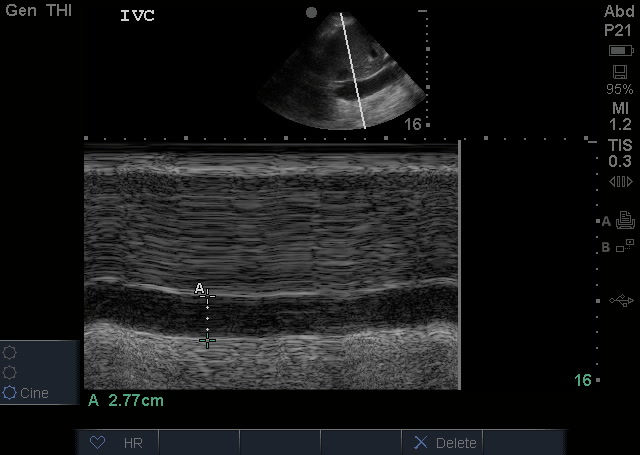

Using M Mode to measure the diameter of the IVC at the area of the hepatic vein inlet (approximately 2-3 cm from the right atria) and seeing that its over 2.5cm with no respiratory variation is like icing on the cake with what we know so far. They stopped the normal saline bolus, and considered pressor support with nitroglycerin/lasix bolus.